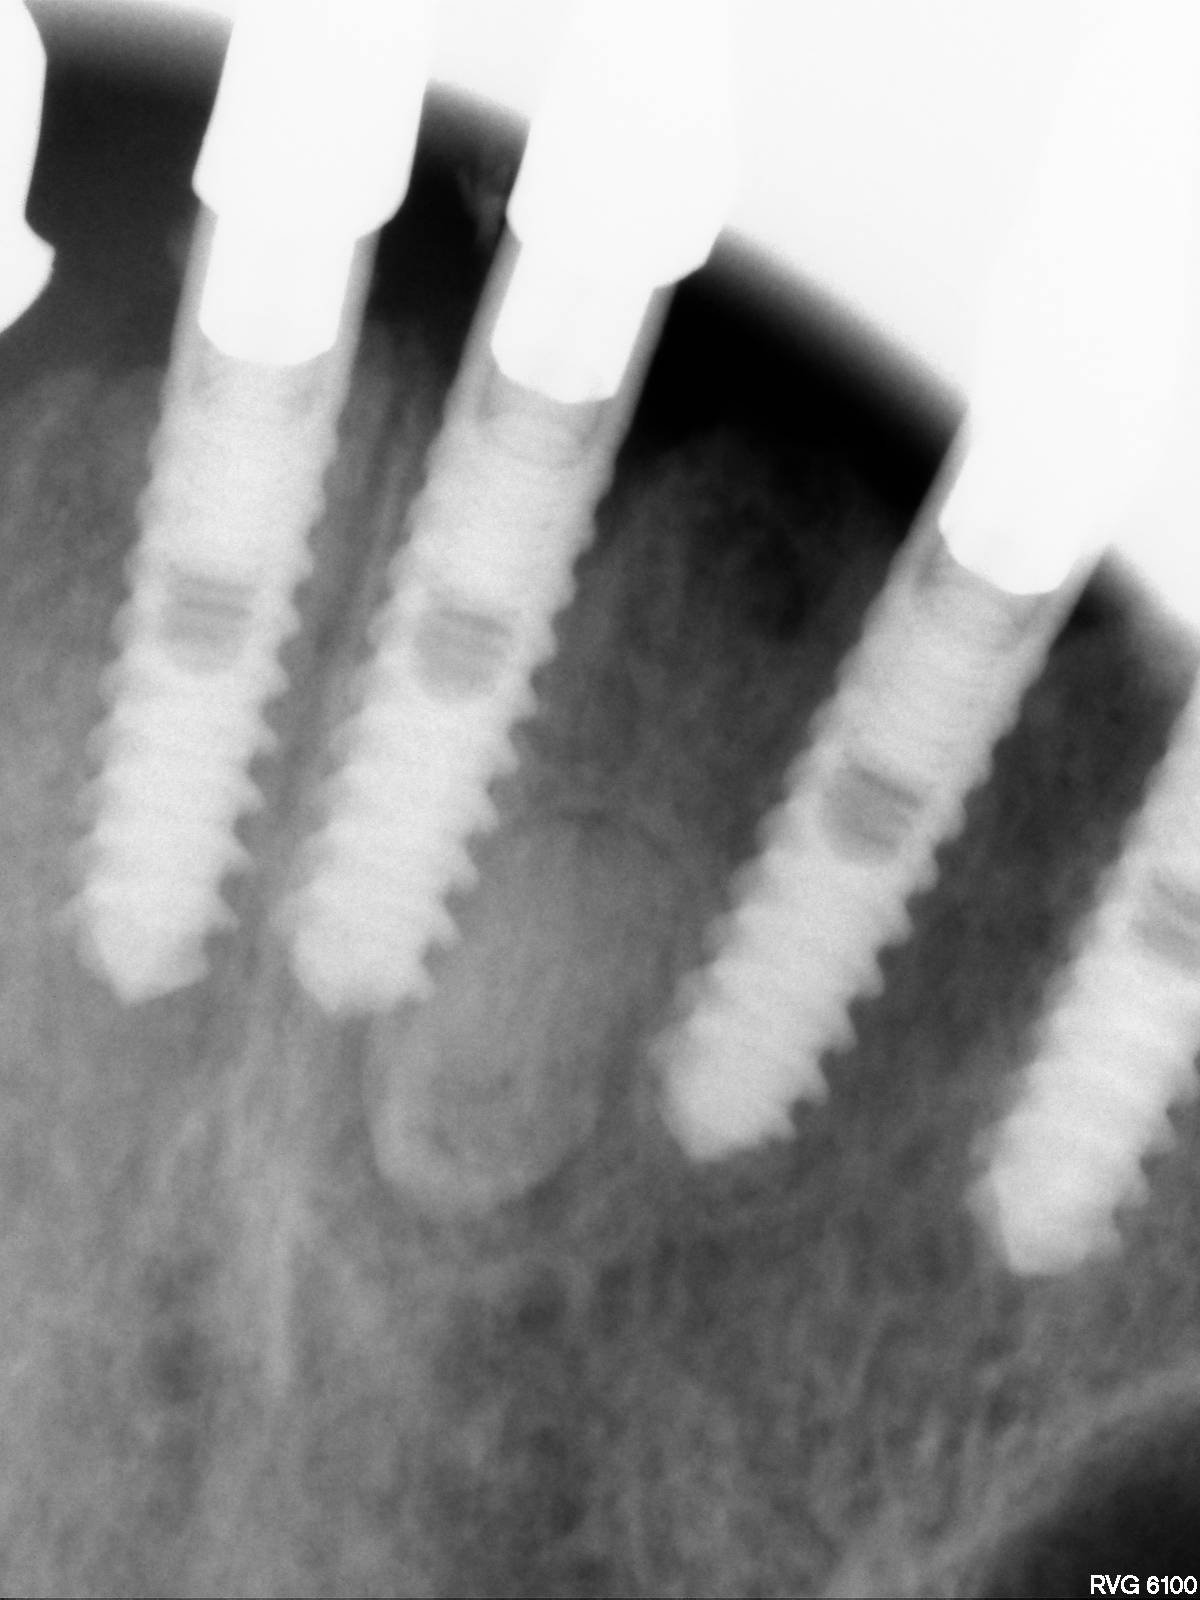

De qué implante se trata?

Buenos días compañeros. Alguien sabría decirme qué implantes son los que se ven en la radiografía? Muchas gracias